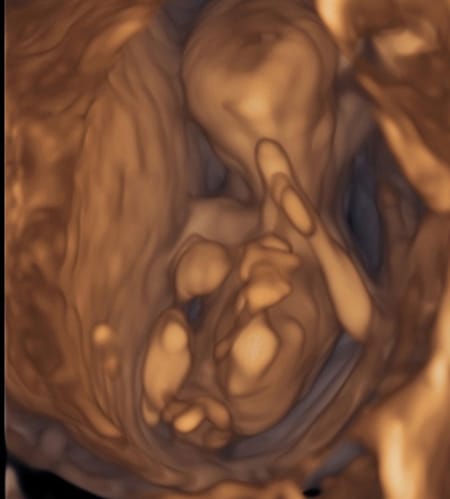

14週目の検診と4dエコー 5月から男の子ママになりました

画像あり 妊娠14週 4dエコーをしたら男の子かもしれないといわれた のんびりストレスフリー ミヤの兄弟子育てブログ